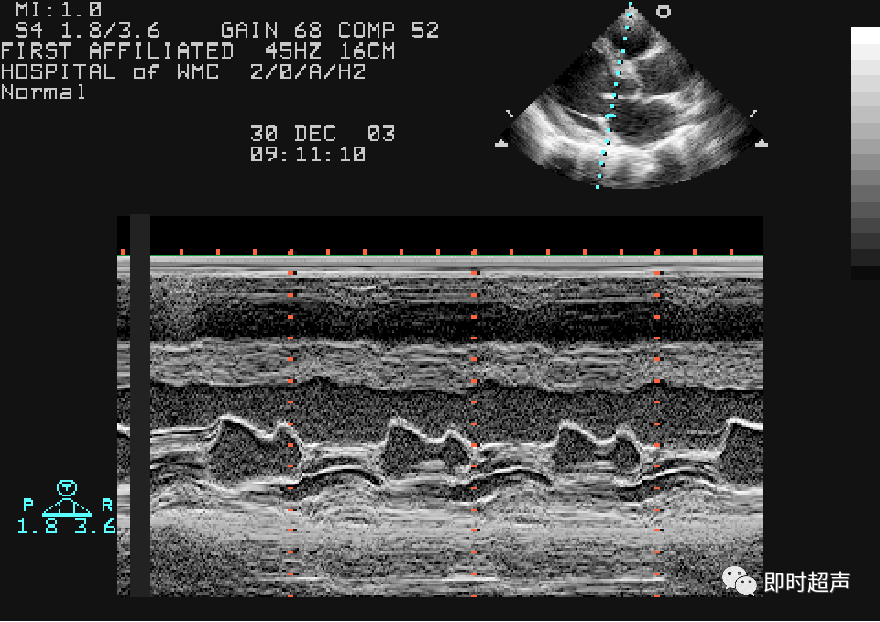

图11 胸骨旁左心室长轴切面及m型超声图像 a:取样线置于2a区;b:m型

b:m型超声心动图显示室间隔运动异常,吸气时室间隔偏移向左心室侧

m型超声心动图二尖瓣波群左房血栓二尖瓣口面积二尖瓣水平短轴观切面

M型超声心动图